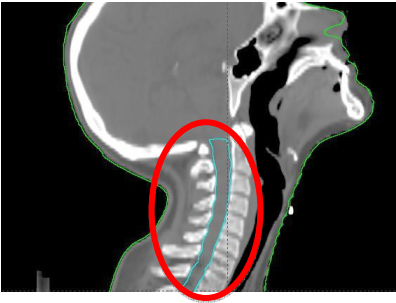

Observe a figura a seguir, que representa um corte sagital reconstruído a partir de imagens tomográficas.

Considerando a imagem, é correto afirmar que a estrutura delimitada é(são)